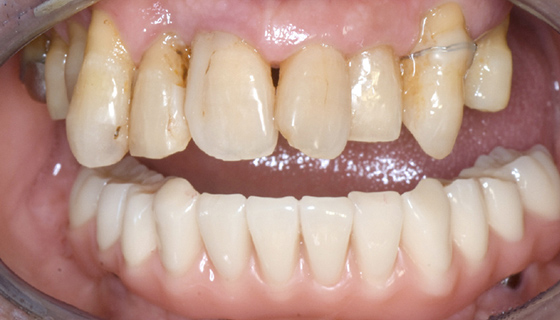

治療前

この症例では下顎の歯周病が特に進行していて、歯がクラグラで噛みにくい為、下の歯を抜歯してオールオン4で治療、上は特に歯周病が進行している左側の大臼歯を抜歯して経過観察することにしました。